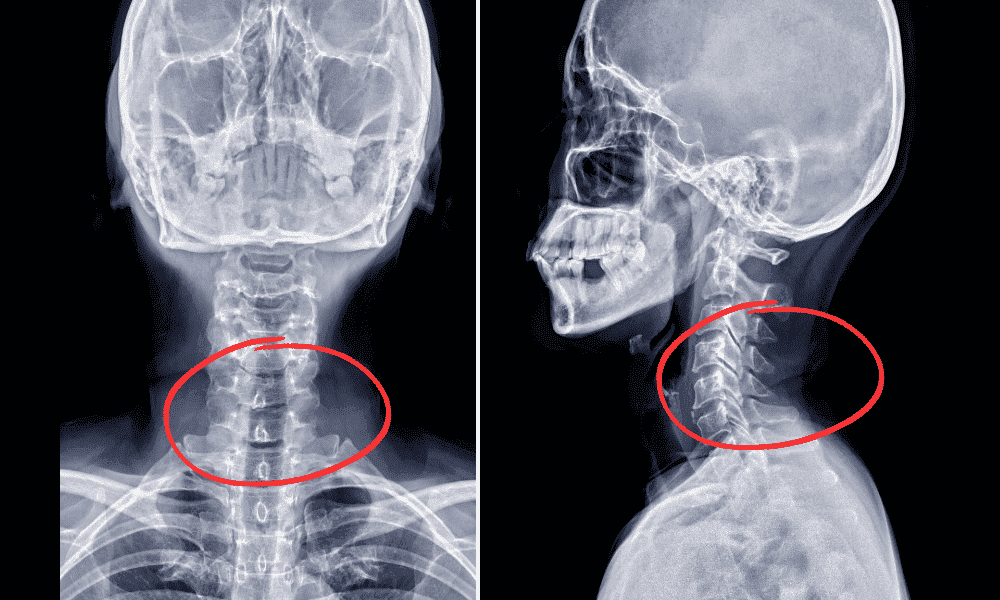

The cervical spine is the upper part of your spinal column, made up of seven vertebrae labeled C1 through C7. The C5-C6 level refers to the disc between the fifth and sixth vertebrae in your neck. This area is crucial because it protects the spinal cord and allows nerves to branch out to your shoulders, arms, and hands.

A herniated disc occurs when the soft inner core of a spinal disc pushes through a tear in the tough outer layer (annulus fibrosis). At the C5-C6 level, this can compress the nerve root, leading to pain, numbness, or weakness that radiates from the neck into the arm or hand. In my 20 years of treating spine conditions, I’ve seen how these symptoms can disrupt daily life for patients in Houston.

Common causes include age-related disc degeneration, sudden injuries, or repetitive strain. Over time, discs lose water and flexibility, making them more prone to herniation. According to Cedars-Sinai, C5-C6 is one of the most frequent sites for disc herniation in the neck.